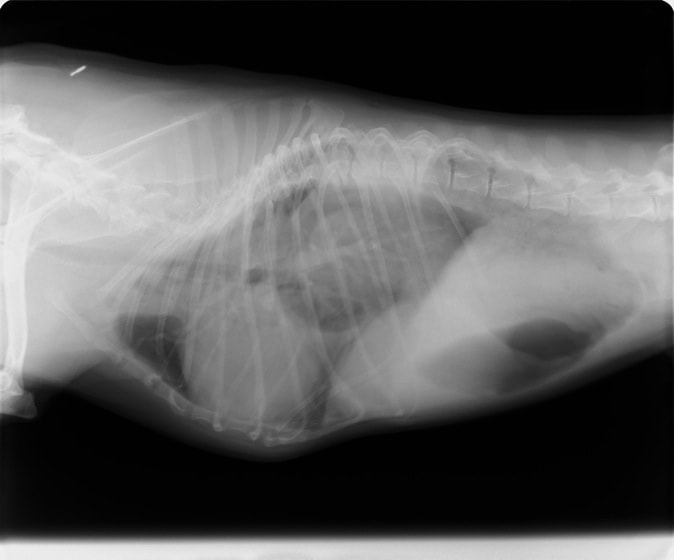

術前のレントゲン

身体検査上、鼓腸を伴う腹囲膨満、口腔粘膜の蒼白などが認められます。確定するには、レントゲン検査の実施が重要となります。その際、著しく拡張した胃が確認され、特徴的な捻転ラインが認められます。